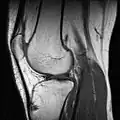

МРТ коленного сустава.

При застарелых разрывах связок симптом «выдвижного ящика» может стать нечётким вследствие развития вокруг места разрыва жировой клетчатки, которая отчасти стабилизирует коленный сустав. Диагноз уточняют при рентгенологическом исследовании. Иногда приходится прибегать к введению контраста в полость коленного сустава или к компьютерной или магнито-резонансной томографии. При необходимости проводят артроскопию: вводят зонд в полость сустава и осматривают сустав изнутри. В качестве первой помощи необходимо обезболить место повреждения, обездвижить коленный сустав с помощью шины и доставить пострадавшего в травмпункт.

Методика исследования

Применяются физикальные методы исследования: осмотр, пальпация, а также сбор анамнеза. Из инструментальных методов для визуализации изменений анатомических структур сустава большое распространение получило МР-исследование. Для оценки целостности и структуры костей, формирующих сустав, предпочтение отдаётся рентгенографии и компьютерной томографии. В настоящее время для диагностики применяют также артроскопию.